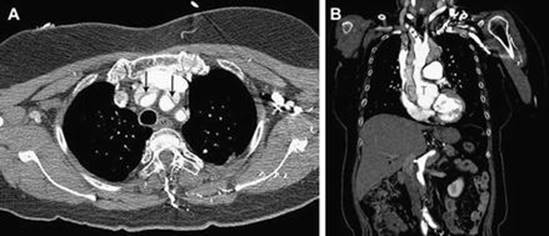

A D-dimer less than 500 ng/mL decreases the likelihood of an acute aortic syndrome [73]. Transesophageal echocardiogram, chest CT, and cardiac MRI are equally useful in diagnosing aortic dissection, though MRI requires the longest examination time, which limits clinicians’ ability to closely monitor an unstable patient (Fig. 15.6) [74]. Chest radiograph and ECG are insufficient to diagnose or exclude an aortic dissection, though mediastinal widening may be noted on chest radiograph [69, 74].

Fig. 15.6

Stanford type A aortic dissection by contrast-enhanced CT. (a) Intimomedial flap (arrows) is noted in brachiocephalic, left common carotid, and left subclavian artery at the level of left brachiocephalic vein. (b) Intimomedial flap (arrows) extending into brachiocephalic artery is noted on coronal image. The contrast enhancement in the true lumen (T) is higher than that of false lumen (F) (Reprinted from Yoo et al. [74], with permission from Elsevier)

Aortic dissections are classified as Type A, involving just the aortic arch, and Type B, occurring below the brachiocephalic vessels [75]. Cardiothoracic surgery (Type A) or vascular surgery (Type B) should be emergently consulted in the event of a positive radiographic finding of aortic dissection.